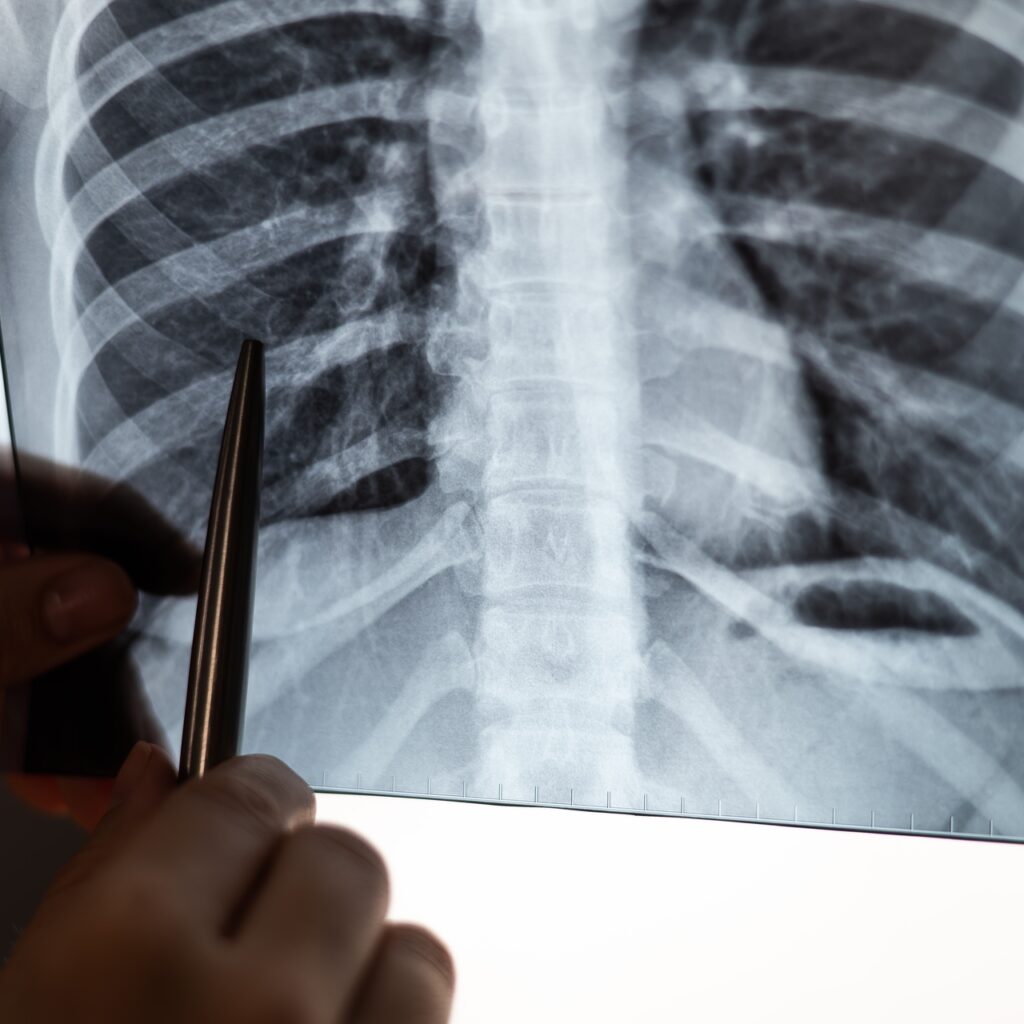

Özlü, Bu yıl Dünya KOAH Günü’nde asıl tema nefesin daralıyorsa KOAH’ı düşün, KOAH’ı aklına getir. Sen de KOAH olabilirsin? Şeklinde bir slogan benimsendi. Bunun çok önemli olduğunu düşünüyorum. Eğer yaşıtlarınıza göre yokuş çıkmakta, merdiven çıkmakta zorlanıyorsanız, eğer her gün öksürüğünüz varsa sürekli balgam çıkartıyorsanız ve sigara da içiyorsanız sizde KOAH olabilirsiniz, bunu aklınıza getirin. Bunun tanısı için bir Göğüs Hastalıkları Uzmanına başvurun. Testleriniz yapılsın, nefes testiniz gerekirse akciğer filminiz çekilsin. KOAH olup olmadığınız ortaya çıksın. Eğer KOAH’ınız varsa da mutlaka onun risk faktörlerine göre gerekli önlemler alınması gerekiyor” uyarısında bulundu.